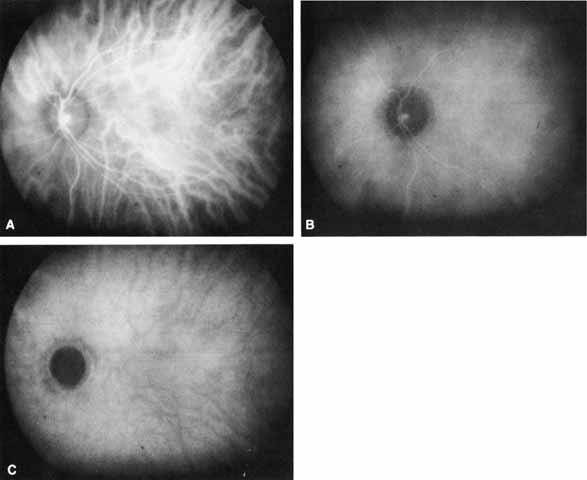

| From a clinical standpoint, ICGA using a digital video system can be grossly

divided into early, middle, and late phases. Although SLO-based

ICGA can be similarly described, investigators using this technique

have concentrated more on the earlier images.12,13 Therefore, the features of a standard ICG videoangiogram based on recent

studies using the standard 1024-line digital systems will be

described.3,4,11 The “early” phase (0–3 minutes after injection) encompasses the period from the first appearance of ICG dye in the choroidal arterial circulation to the point of maximal ICG choroidal hyperfluorescence, usually occurring within the first minute after the injection of dye (Fig. 1A). During this phase, both medium and large choroidal arteries and veins are well visualized beneath the hyperfluorescent retinal vasculature. Individual choriocapillaris vessels cannot be distinguished. The areas surrounding middle and large choroidal vessels appear relatively hypofluorescent. This “pseudohypofluorescence” is, at least in part, a result of a smaller volume of blood in the choriocapillaris compared with the larger vessels, with the illumination intensity adjusted for the strongest portion of fluorescence. In the “middle” phase of the angiogram (5–15 minutes after injection), the choroidal veins become less distinct as a nearly homogeneous, diffuse choroidal fluorescence emerges (see Fig. 1B). The fluorescence from the retinal vessels also begins to attenuate. Lesions that demonstrate abnormal hyperfluorescence on ICGA typically begin to stand out in contrast to the fading surrounding normal background fluorescence by this point in the study. In the “late” phases (beyond 18–22 minutes), all details of normal retinal and choroidal vessels are lost as the hyperfluorescence fades even further (see Fig. 1C). The choroidal vessels now stand out in relief as hypofluorescent channels and retinal vessels are no longer visible, and the optic nerve head is dark. There is maximal contrast with any abnormal hyperfluorescent lesions. The edges of such lesions may exhibit some “fuzziness” at this stage, apparently from limited dye leakage. For the standard ICGA, 25 mg (12.5 to 50 mg) of ICG dye in the manufacturer's diluent is administered intravenously in a bolus fashion, similar to intravenous fluorescein angiogram protocols. Images are typically obtained at several second intervals until the retinal and choroidal circulations are maximally hyperfluorescent and then at approximately 30- to 60-second intervals for the first few minutes of the study to capture images through the early phase of the angiogram. Subsequent images are typically taken between 8 and 12 minutes for the middle phase and then between 18 and 25 minutes for the late phase. Most importantly, abnormal ICG hyperfluorescence is sufficiently identifiable by 25 minutes, but, occasionally, images obtained 30 to 40 minutes into the study are helpful. To image retinal and choroidal vessels in the late phase of the angiogram, a technique of reinjecting a small amount of ICG dye at 30 to 40 minutes into the study has been described.33 The available software packages of most digital videoangiogram systems have image-enhancing and image-tracing capabilities. Limited improvement of image contrast can be obtained with various enhancement techniques. The ability to align and superimpose images and tracings (“warp tracing”) can be helpful in determining the location or size of a particular angiographic finding, with respect to other anatomic structures (Fig. 2).4,11

|